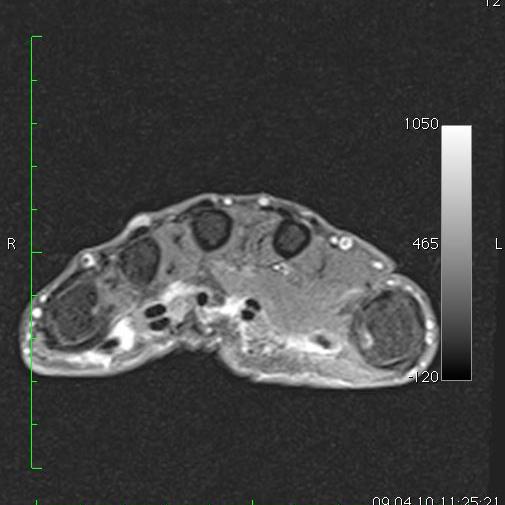

Die MRT ist inzwischen unverzichtbarer Bestandteil der Diagnostik am Bewegungsapparat. Muskeln, Sehnen, Bänder, Knochen und Knorpel, sowie deren Krankheitszustände lassen sich in unvergleichlicher Weise differenzieren. Einige Krankheitsbilder wie z.B. das "traumatische Knochenödem" oder die knöcherne Stressreaktion sind überhaupt erst durch die MRT bekannt geworden.